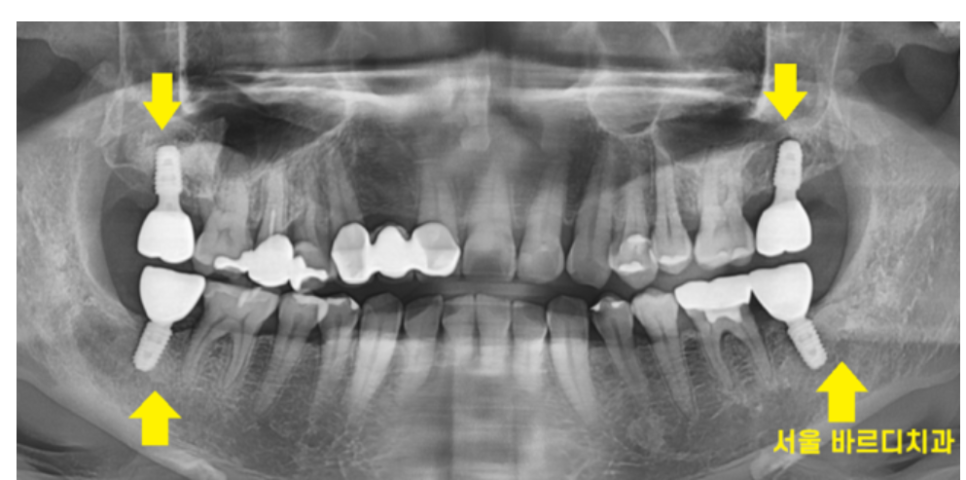

양쪽 맨 끝 어금니가 위아래로 발치된 환자분입니다.

한쪽도 아니고 양쪽으로 위아래 모두

끝에 치아만 발치하셨으니